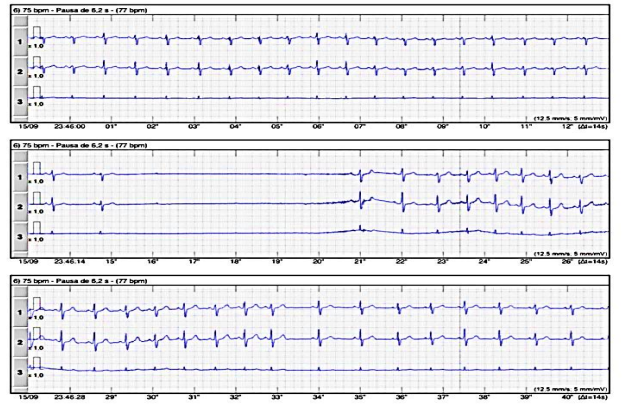

Paciente obeso, sem cardiopatia estrutural, 38 anos, numa avaliação de rotina, cujo Holter 24 horas apresentou no exame o traçado representado na imagem abaixo.

Diante dos dados apresentados nesse caso, a hipótese diagnóstica é de